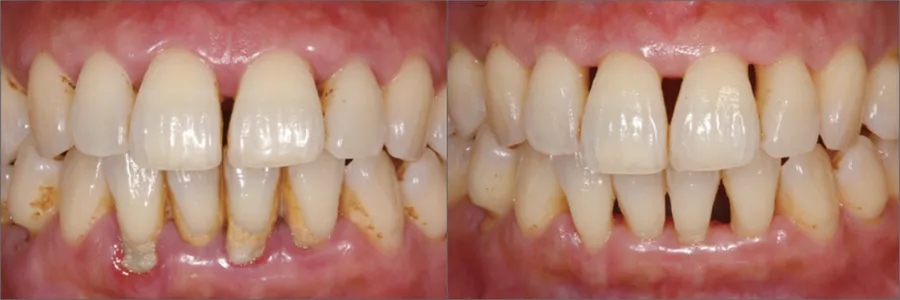

上の写真のように、スケーリングは目で見える「歯肉縁上」部分に付着した歯石や歯垢を除去する治療方法です。

一方、ルートプレーニングは、上の写真のように「歯周掻爬術」または「歯肉縁下掻爬術」とも呼ばれ、目に見えない歯と歯茎の境界面「歯肉溝」にたまった歯石を除去する方法です。歯根面を滑らかにし、再付着を促進することを目的としています。